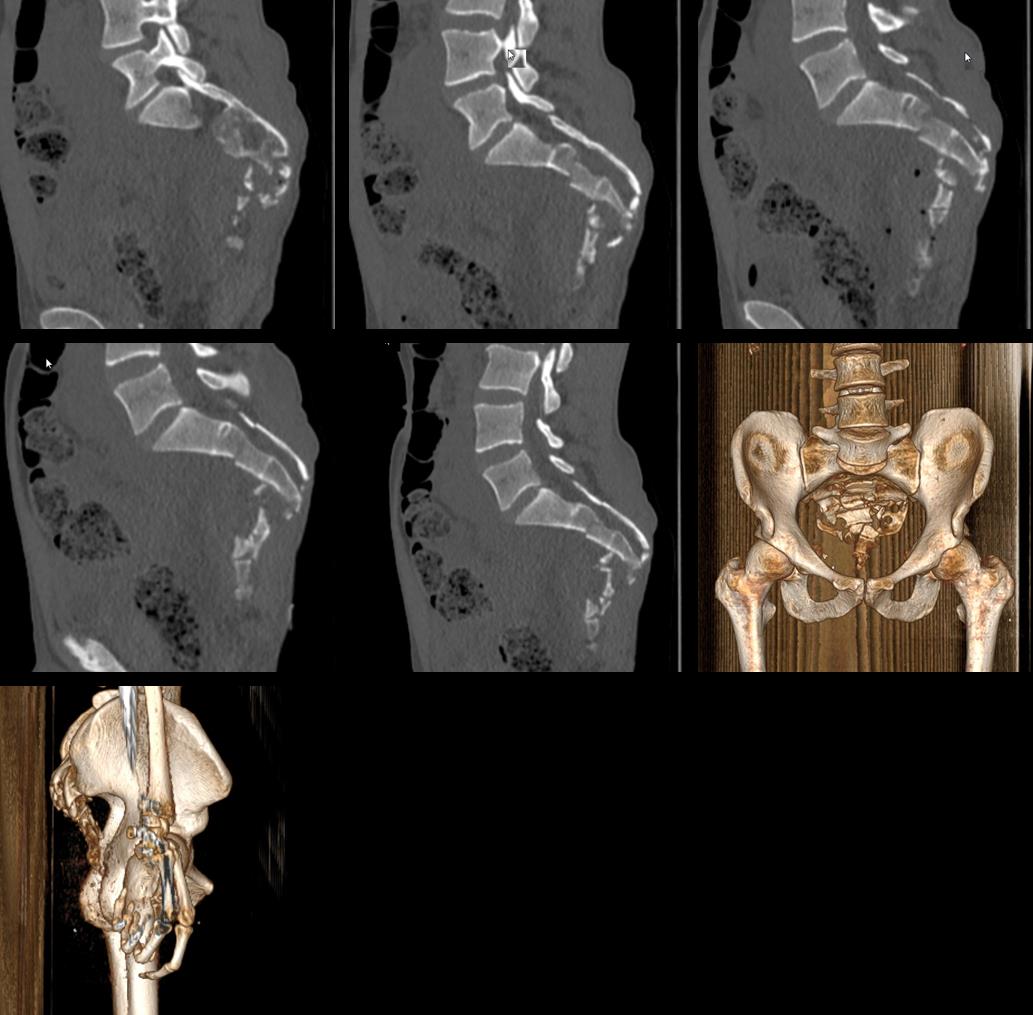

Коллеги, подскажите , пожалуйста , тактику при лечении таких переломов крестца. Травма получена в ДТП, от 06.09.2019г. не справился с управлением мотоциклом, врезался в бордюр и упал с мотоцикла. Сознания не терял, обстоятельства травмы помнит. Имеется травматическая отслойка кожи в области ягодиц. Открытый перелом костей правой голени в средней трети (тип 3А по Gustilo-Anderson). Мы планируем идти на репозицию и остеосинтез. Опыт оперативного лечения переломов крестца есть, но ранее были простые поперечные переломы. С такой степенью фрагментации я еще не сталкивался. Буду искренне признателен за советы.

Данный перелом нужно рассматривать не с позиции травматолога, а с позиции спинального хирурга. Перелом относится к типу А3 и нуждается (при наличии неврологии) в ляминоэктамии и открытой фиксации двумя пластинами. Но при таком характере костных разрушений, боюсь представить, что с мягкими тканями.